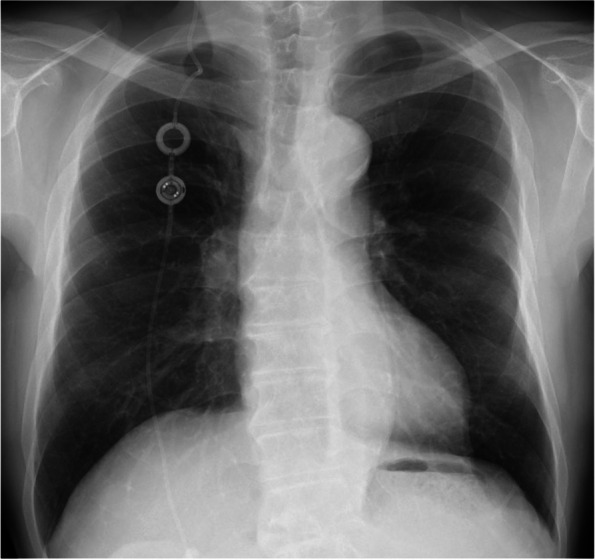

Case presentation: A 75-year-old male with a history of VP shunt for a fourth ventricle obstruction underwent cerebral vascular anastomosis in the prone position. His preoperative level of consciousness was clear. The surgery under general anesthesia was completed without any particular issues. After discontinuation of anesthesia, the patient did not awaken for over an hour. Postoperative CT revealed exacerbated hydrocephalus, likely from VP shunt occlusion. After pumping the reservoir of the VP shunt, the patient regained consciousness. He was extubated and discharged from ICU on the second postoperative day with no neurological issues.